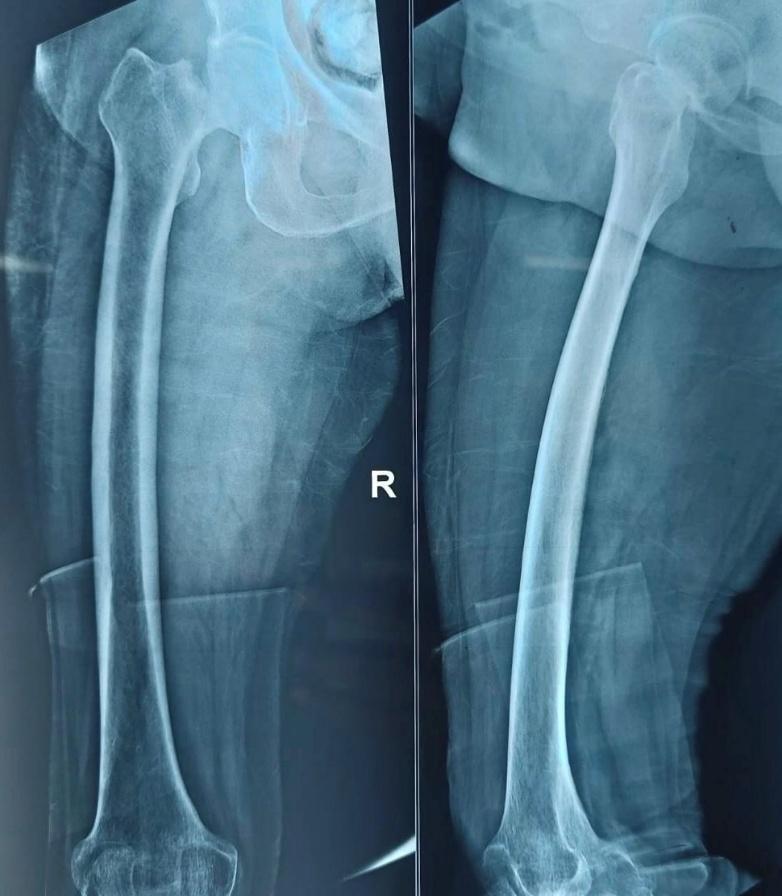

All patients underwent detailed history taking, comorbidity assessment, and clinical examination. Standard radiographs (anteroposterior pelvis and lateral hip views) were obtained. Laboratory evaluations included hemogram, renal and liver function tests, ECG, and chest radiography. Preoperative counseling explained expected outcomes and postoperative rehabilitation. A representative preoperative fracture radiograph is shown in Figure 1.